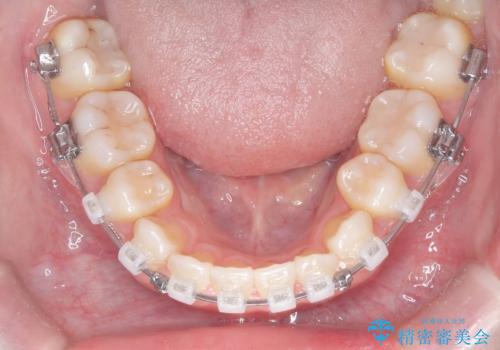

- クリア装置

- 治療計画

上下左右の第一小臼歯を抜歯し、クリアブラケット(白い装置)とメタルワイヤーを使用して矯正を開始。初期には犬歯のアーチ内への整列を優先し、中盤からは前歯と奥歯の咬合関係の調整を進めました。審美性に優れた装置を使用したことで、治療中も目立ちにくく、見た目へのストレスが少ない点も評価されています。全体の治療は1年半で完了し、見た目・噛み合わせともに大きく改善。患者本人も「短期間でここまで変わるとは思わなかった」と満足されていました。